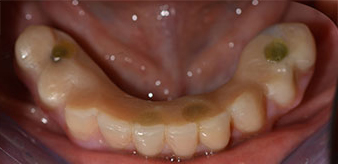

Die 64-jährige Patientin wurde mit einer Unterkiefer-Restbezahnung 38, 33 und 43 und einer klammerbefestigten Interimsprothese im Unterkiefer vorstellig (Abb. 1 und 2).